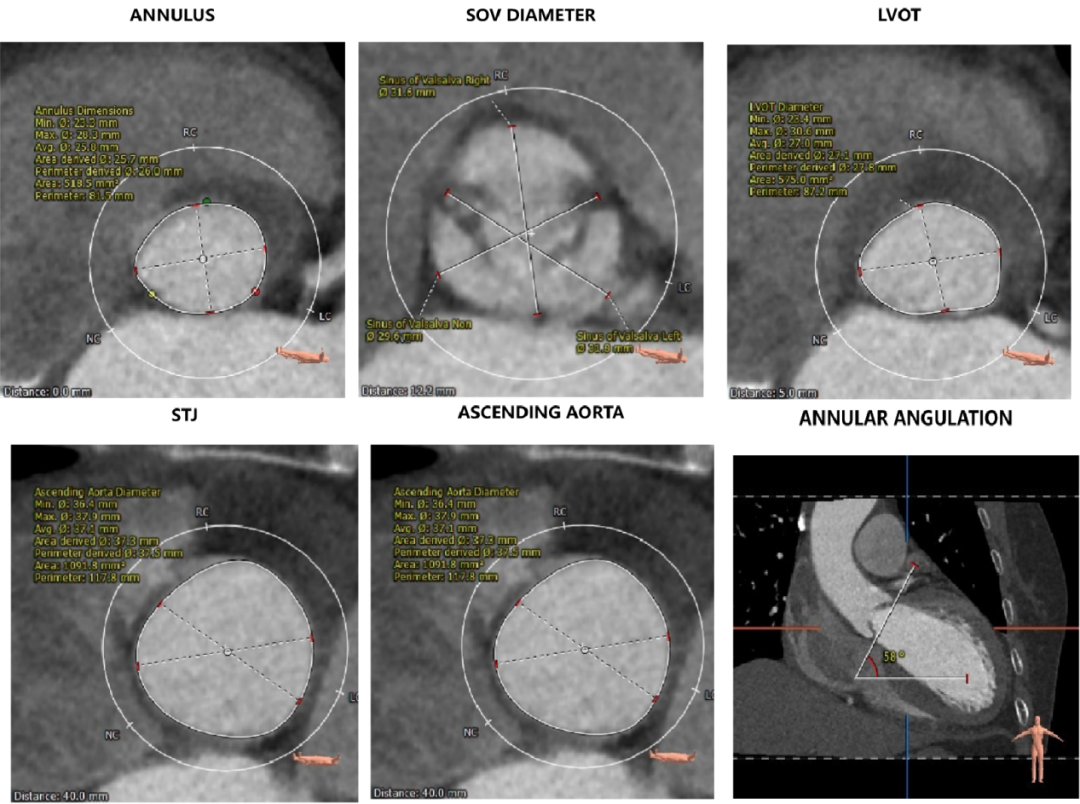

主动脉根部评估:

CT数据显示该患者为三叶三窦式主动脉瓣。

1. 主动脉瓣瓣环周长70.6mm,平均周长径 22.5mm,SOV:28.5mm*28.7mm*29.9mm,瓣叶增厚,瓣上钙化明显。

2. 左冠开口高度14.3mm,右冠开口高度16.4mm,高度可,根据瓦氏窦内径和瓣叶长度综合判断,冠脉堵塞风险小,双侧冠脉钙化严重。

钙化评估:

中度钙化,HU850积分472m㎡,RCC钙化最严重,其次为LCC、NCC。

心室情况:

左室前后径28.7mm,左室最小径13.6mm,瓣环下6mm存在心肌膨出,

主动脉瓣瓣环周长81.5mm,平均周长径 26mm,SOV:31.8mm*31.5mm*29.6mm,瓣叶增厚,瓣上未见明显钙化,瓣环水平夹角58°。

左冠开口高度18.8mm,右冠开口高度21.9mm,高度可,根据瓦氏窦内径和瓣叶长度综合判断,冠脉堵塞风险小。

HU850钙化积分6mm³